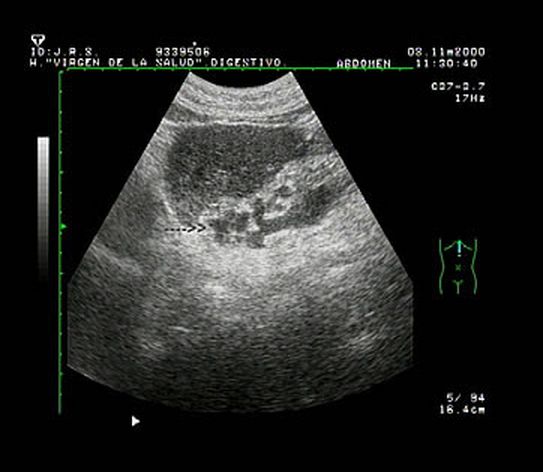

1.5. Anomalías vasculares